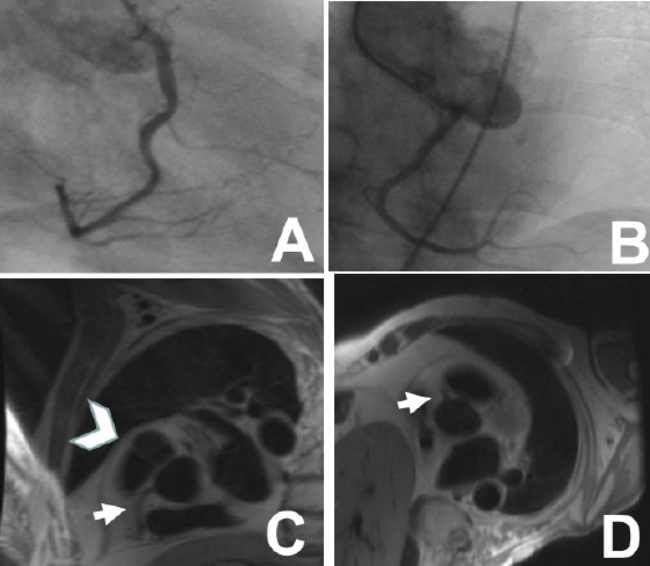

A total of 37 original catheterization reports were available for review; we requested (but did not receive) the official report in the other 13 cases. The diagnosis was considered “correct” if the origin/proximal course was clearly identified in the official report. The diagnosis was considered “incorrect” if the origin/proximal course was either not identified or identified incorrectly, as compared with CMR. Referring angiographers made the correct diagnosis of the origin of the ACA in 30 of 37 patients (89%) and of the proximal course of the ACA in 10 of 37 patients (27%). The expert interpreters of CCA made the correct diagnosis of the origin of the ACA in 49 of the 50 patients (98%) and of the proximal course of the ACA in 49 of the 50 patients (98%). There was no significant difference between the different interpreters in determination of the origin. However, the rate of correctly identifying the proximal course of the ACA was significantly lower in the Referring group (P<.001). Notably, 3 patients were ultimately determined to have no ACA by CMR. In 2 of these patients, the Expert group correctly identified the cases as normal. In 1 patient (#29) (Table 1; Part 1, Part 2 and Figure 1), the Expert group identified an anomalous RCA arising from the LSV with an interarterial course, while CMR showed a normal origin of the vessel from the right sinus of Valsalva (RSV), although near to the commissure with the LSV. In this case, a standard left anterior oblique (LAO) view in the catheterization session was not obtained, and it was felt in retrospect by the Expert group that inclusion of this usual view would have increased the likelihood that they would have interpreted the study as “normal.” In comparison, Figure 2 shows non-selective aortogram images in patient #22, in whom the RCA arising from the LSV with interarterial course was seen on the aortograms, and confirmed on cardiac MRI in a 3 T scanner; the LAO view clearly shows that the vessel does not arise from the RSV.